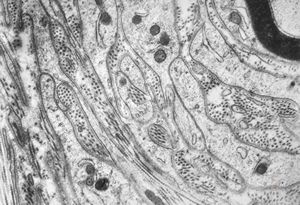

F,12y. | hypertrophic (onion bulb) neuropathy - n.suralis

F,12y. | hypertrophic (onion bulb) neuropathy - n.suralis

F,12y. | hypertrophic (onion bulb) neuropathy - n.suralis